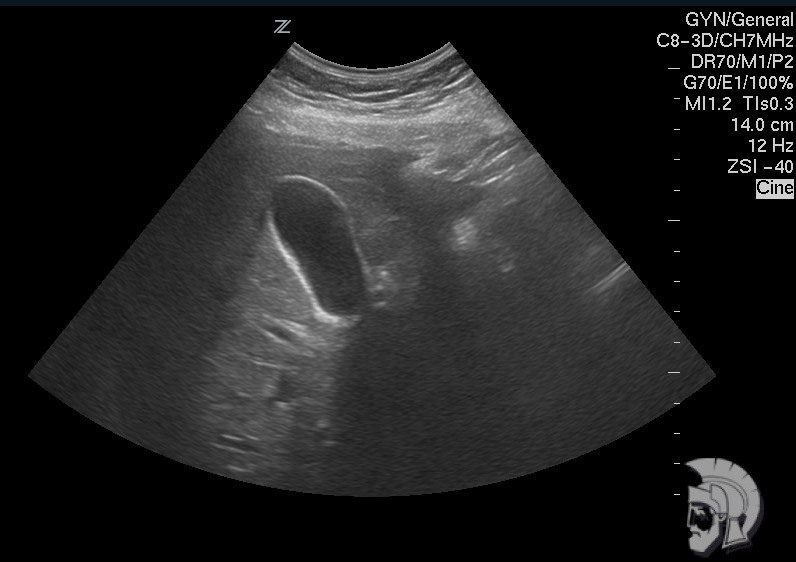

| Фото желчного пузыря. Перетяжка в нижней трети желчного пузыря мужчины 43 лет |

Обратите внимание на совершенное качество фотографий, свидетельствующих об экспертном классе наших аппаратов УЗИ!

Использование ультразвуковых аппаратов экспертного класса с режимами энергетического ДОППЛЕРа и цветового допплера позволяет врачам Курортной клиники мужского здоровья выявлять патологические изменения на ранних этапах.